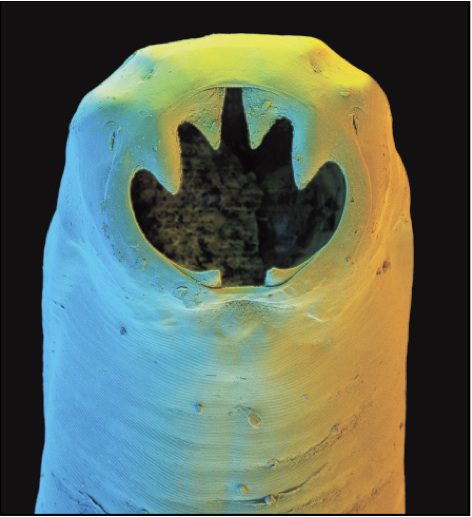

Photo Credit: David Scharf

- Hookworm mouth (jpg)